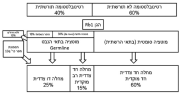

| 07:42, 12 באוגוסט 2023 | רטינובלסטומה 2.png (קובץ) |  |

79 קילו־בייטים | Motyk | 1 | |

| 18:29, 11 באוגוסט 2023 | רטינובלסטומה1.png (קובץ) |  |

83 קילו־בייטים | Motyk | 1 | |